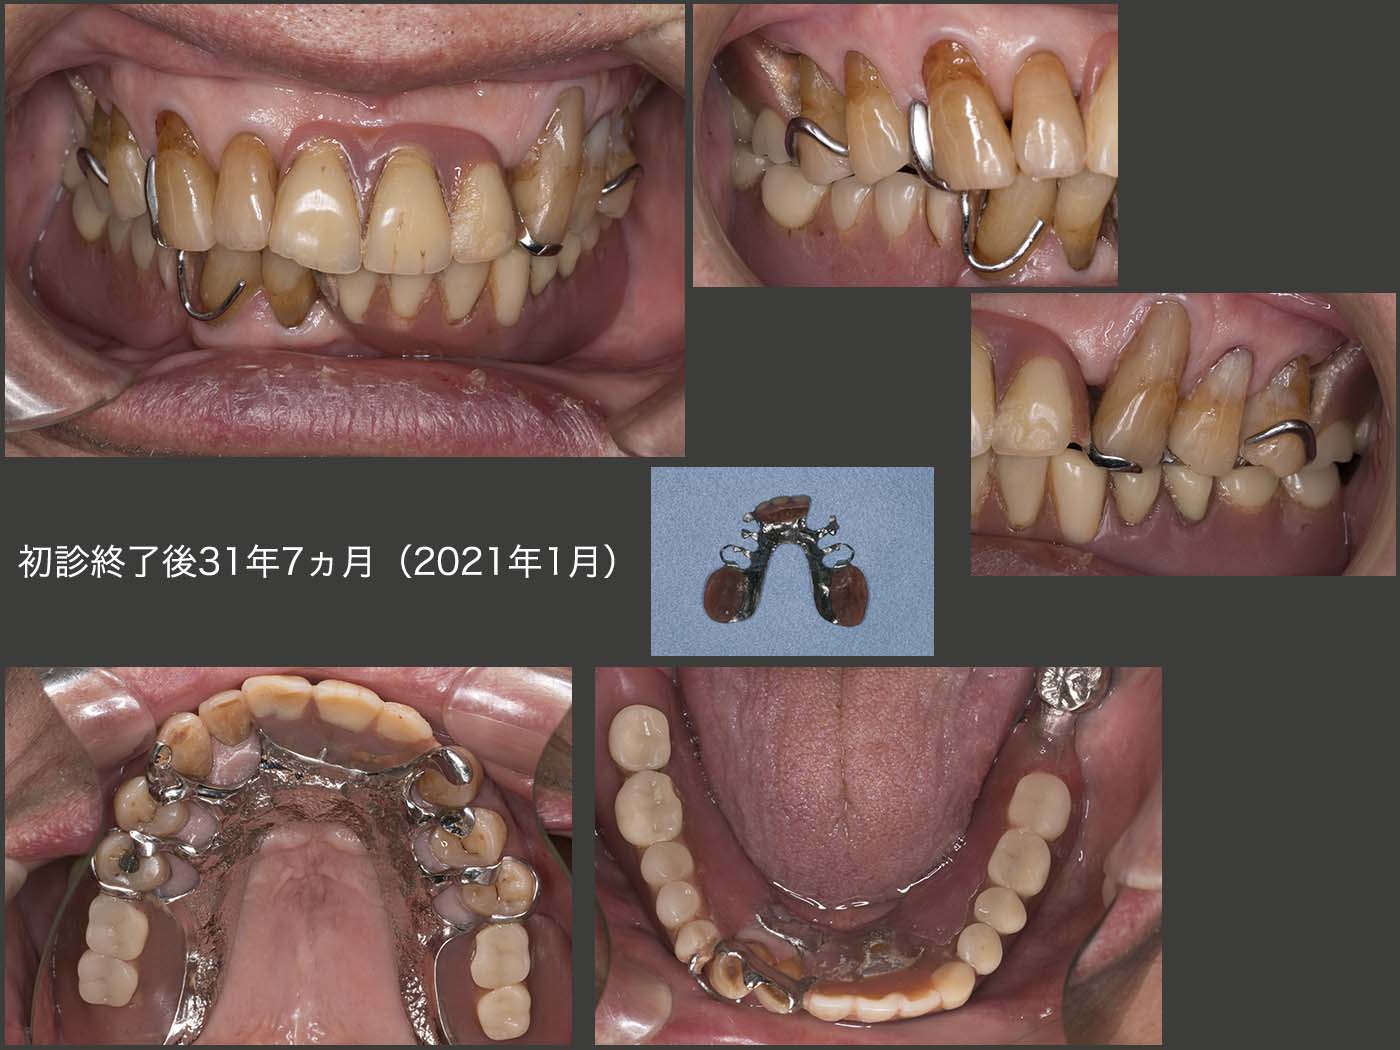

2021年1月,初診終了後31年7ヵ月の状態.上段左に示す1995年8月のデンタルX線写真と比べて,25年5ヵ月後となる上段右に示す21年1月の状態は,左下1,2が失われ,右上5が根面カリエスから抜髄(00年4月)された以外はほとんど変化がみられなかった.特に,歯周ポケットに変化がみられなかったことから,歯の清掃性はまずまずであり,患者さんが力をあまり加えないで上手に咀嚼できたことが功を奏したのではないかと推察する.なお今回,左上の4,5の根面カリエスにコンポジットレジン充塡を行った.

2021年1月,初診終了後31年7ヵ月の義歯装着時の状態.下顎の義歯においては,2〜3年に1回の割合で,義歯が破折し,その度に修理およびリライニングを行っている.一般的に支台歯が片側に偏った症例は,義歯の維持安定を得るのが難しい.しかし,たまに修理およびリライニングを行う以外,咀嚼にそれ程不満を訴えなかったことは,左下8の存在が大きいと思われる.(上下顎に犬歯が4本残存している症例においては,義歯の維持安定が得られやすい.今回は,左下3の役目を左下8が多少なりとも担ってくれたと考えている.)

これに対して,上顎においては,スライド6で述べた両側犬歯の支台装置交換以外に修理を行った記憶がない.また,31年7ヵ月,一度もリライニングを行っていないことは,大変な驚きである.咬合力の大きさの程度,対合歯の加圧要素の存在,受圧要素として,支台歯が両側にあるか否か等の条件が良ければ,長期間義歯が安定すると教えていただいた.